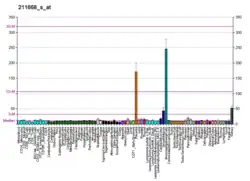

The PLAU gene encodes a serine protease (EC 3.4.21.73) involved in degradation of the extracellular matrix and possibly tumor cell migration and proliferation. A specific polymorphism in this gene may be associated with late-onset Alzheimer disease and also with decreased affinity for fibrin-binding. The protein encoded by this gene converts plasminogen to plasmin by specific cleavage of an Arg-Val bond in plasminogen. This gene's proprotein is cleaved at a Lys-Ile bond by plasmin to form a two-chain derivative in which a single disulfide bond connects the amino-terminal A-chain to the catalytically active, carboxy-terminal B-chain. This two-chain derivative is also called HMW-uPA (high molecular weight uPA). HMW-uPA can be further processed into LMW-uPA (low molecular weight uPA) by cleavage of chain A into a short chain A (A1) and an amino-terminal fragment. LMW-uPA is proteolytically active but does not bind to the uPA receptor.[8]